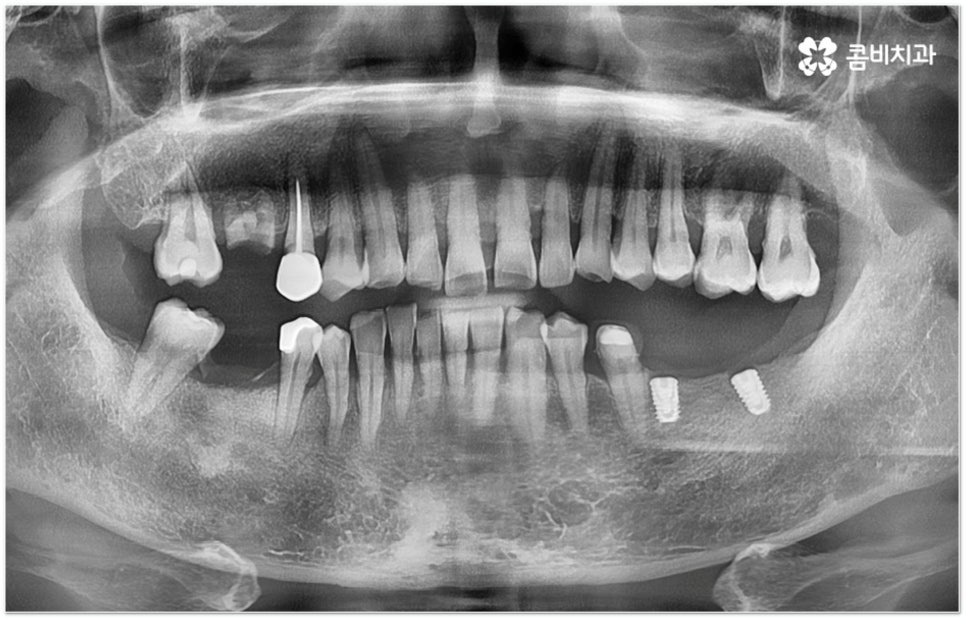

그러나 임플란트는 잇몸뼈에 직접 심어서 고정시키는 방식인 만큼 만약 환자분의 잇몸뼈가 부족하거나 치아가 빠진 후 오랜 시간이 지나 이미 잇몸뼈 소실이 상당 부분 이루어진 상태라고 한다면 먼저 골이식을 통해 이를 보충한 후 식립을 진행하는 뼈이식임플란트 방식을 이용할 필요가 있어요. 골이식 과정은 바탕이 되는 잇몸뼈의 밀도나 높이, 두께가 부족한 부분에 이식 재료를 심어주어 뼈를 재건해 주는 것인데 충분한 시간을 두고 무리하지 않게 진행하는 것이 뼈이식임플란트 수술의 성공률 및 안정적인 지속성을 높일 수 있는 방법이 될 거예요.

뼈이식임플란트 가 필요한지 살펴볼 때 3D CT 촬영과 같은 정밀 진단을 통해서 환자분의 잇몸뼈 두께 등 치조골 상태 뿐 만 아니라 구강 구조, 치아 및 잇몸 상태, 신경관 위치, 상악동까지의 거리 등을 꼼꼼하게 확인하여 치료 계획을 세우고 필요하다면 구강 질환에 대한 치료나 상악동 거상술 등을 선행하며 잇몸뼈 부족에 대해서도 골이식 과정을 먼저 진행하게 되는데요, 이러한 뼈이식임플란트 시술은 상당히 고난도의 복잡한 치과 진료인 만큼 관련 임상 경험이 풍부한 의료진과 함께 하는 것이 굉장히 중요하며 또한 수술 후 관리 면에서도 더욱 신경을 써 주시길 당부드리고 있어요.